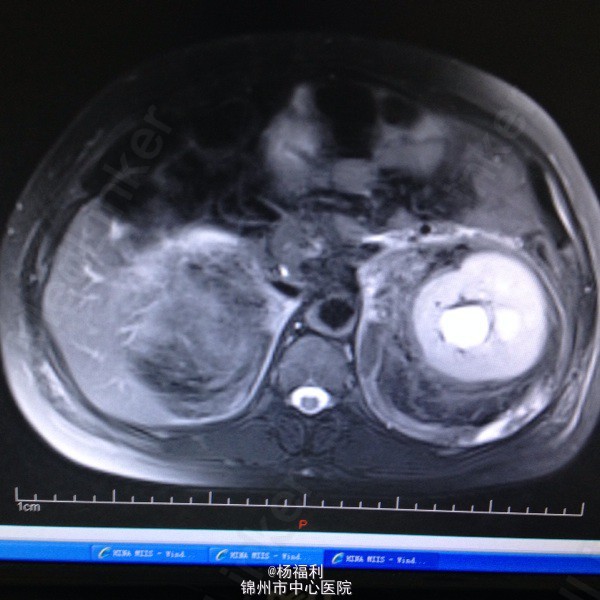

44岁女患。为消化科我会诊患者。 现病史:以上腹痛9小时为主诉入院。无发热及寒战、噁心未呕吐,无腹泻及黑便。 既往史:双眶炎性假瘤2年,口服激素治疗,并补钾。

查体:上腹部压痛,无反跳痛、右侧压痛明显,右肾区叩击痛,左肾区轻叩击痛,双输尿管走形区无压痛。 辅助检查;泌尿系彩超:双肾积水。 血白细胞:9.99*10^9。 肾功能正常。 全腹部ct及MRU检查:见图片。

诊断;真的不知道是啥病。 处理:暂时止痛处理。双肾病变。不知从哪里下手。